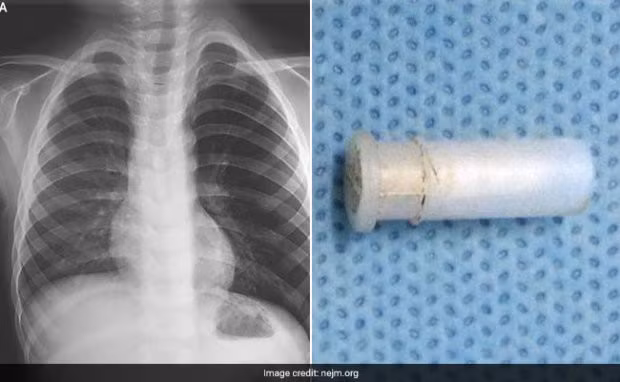

| Hình ảnh chụp phổi cậu bé và dị vật. |

Cha mẹ cậu bé cho biết, cậu bé đã đùa nghịch với một cái còi đồ chơi trước khi bắt đầu ho liên tục kèm theo những tiếng rít như tiếng huýt sáo. Các bác sĩ chụp X-quang vùng ngực của cậu bé, phát hiện thấy phổi trái của cậu bé bị hyperinflated (hiện tượng phổi căng phồng quá mức), lý do là do một vật cản đã chặn đường dẫn khí vào phổi, gây tắc đường hô hấp.